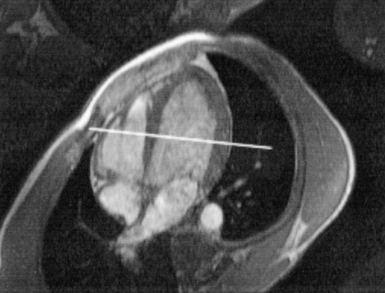

The right atrium forms the right border of the heart and receives deoxygenated blood from the body via the superior and inferior venae cavae and from the coronary sinus and cardiac veins that drain the myocardium. A small muscular embryonic appendage, the right auricle, projects upward and toward the left from the right atrium, covering the root of the aorta (Figure 6.40). The right ventricle lies on the diaphragm and comprises the largest portion of the anterior surface of the heart. It receives deoxygenated blood from the right atrium and forces it into the pulmonary trunk for conveyance to the lungs. Projecting off the inferior surface of the ventricular walls are conical-shaped projections of cardiac muscle called papillary muscles that anchor the cusps of the tricuspid valve to the right ventricle (Figure 6.39). The left atrium lies posterior to the right atrium and is the most posterior surface of the heart. It also has an embryonic appendage, the left auricle, that projects to the left of the pulmonary trunk over the superior surface of the heart. The left atrium receives oxygenated blood directly from the lungs via the four pulmonary veins (two on each side). The left ventricle forms the apex, left border, and most of the inferior surface of the heart. It receives oxygenated blood from the left atrium and pumps it into the aorta for distribution throughout the systemic circuit. The myocardium of the left ventricle is normally three times thicker than that of the right ventricle, reflecting the force necessary to pump blood to the distant sites of the systemic circulation (Figures 6.41 through 6.52). Two papillary muscles project from the ventricular walls to anchor the bicuspid valve to the ventricle (Figures 6.39 and 6.47).

Figure 6.43 Axial, T1-weighted MR scan of left atrium.

Key: RV, Right ventricle; LV, left ventricle; LA, left atrium; RA, right atrium.